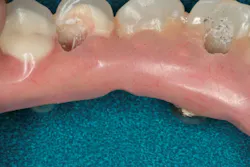

I removed the bridge to find the intaglio packed with food debris. The patient’s tissue was inflamed (figure 3), and she had developed a fungal infection. This could have been avoided with better presurgical preparation, adequate bone reduction, and proper vertical space development, which would have allowed the lab to make a hygienic intaglio (figure 4). Note the smooth and flowing intaglio surface in Figure 4. This is a bridge that can be easily maintained by the patient and hygienist.

Figure 4: Ideally convex intaglio surface for easy cleaning

- Ensure that the intaglio surface of the bridge is convex and hygienic.

- Avoid flanges on the intaglio. If they are absolutely necessary for support of the denture teeth or for esthetics, keep them 2 mm to 3 mm or less in height and only on the facial. This will minimize food retention.